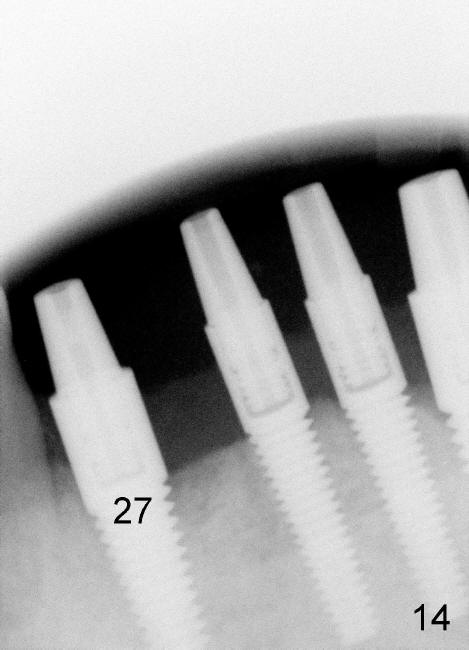

The 4 anterior implants appear to have been osteointegrated 5 months postop (Fig.14,15). More gingiva has covered the top portion of the implants (Fig.16). Ball abutments are placed for an overdenture (Fig.17).